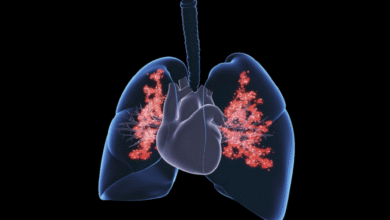

عدوى رئوية شائعة ترفع خطر الإصابة بأمراض القلب

وجدت دراسة دنماركية حديثة أن عدوى رئوية شائعة قد ترفع خطر الإصابة بأمراض القلب لدى البالغين بصورة ملحوظة. وأظهرت الدراسة…